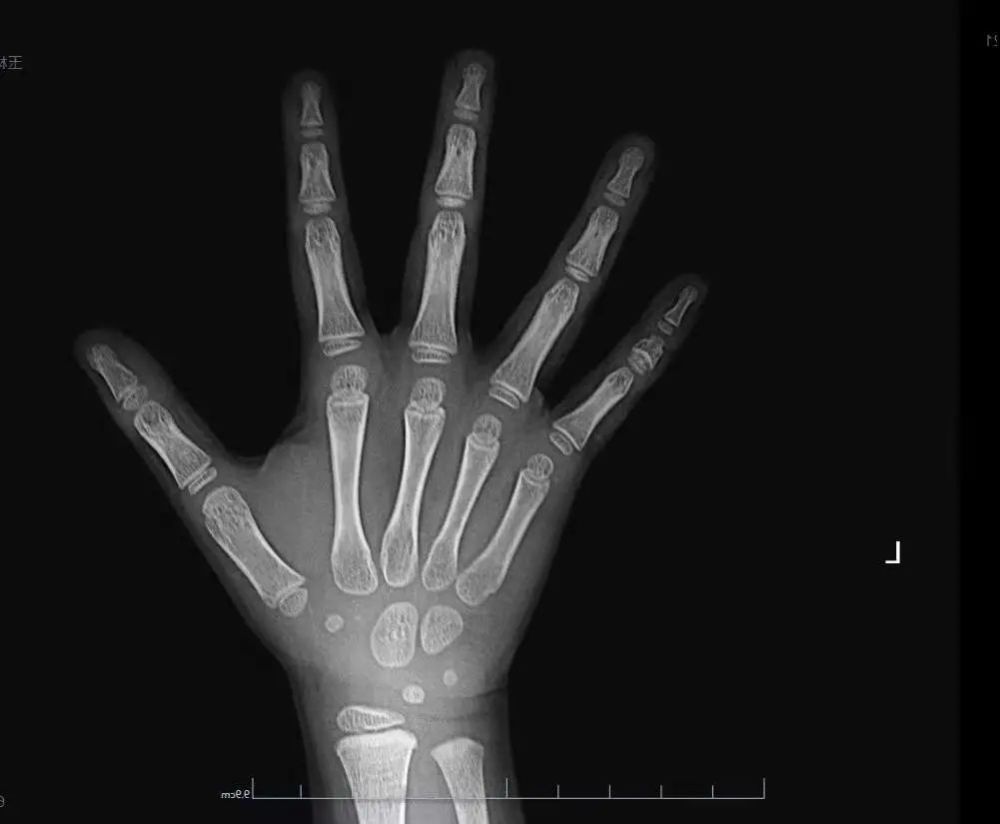

男,16岁,求看一下骨龄,我大概还能长几厘米